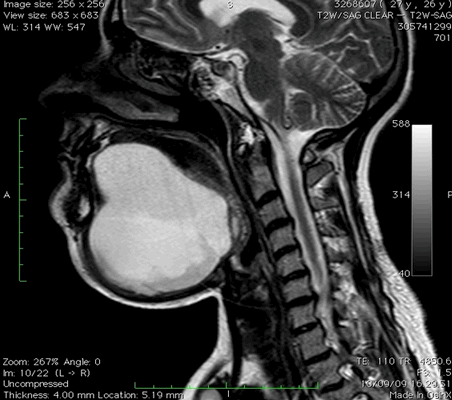

- Это немного разные вещи. МРТ шейного отдела позвоночника - узконаправленное обследование. При выполнении данной процедуры видны только позвоночник и спинной мозг. МРТ мягких тканей шеи - обследование более расширенное. При его проведении просматриваются и оцениваются мышцы, слюнные железы (подъязычная, нижнечелюстная, околоушная), щитовидная железа, пищевод, гортань, а также межфасциальные пространства. Просматривается также корень языка, грушевидные синусы, лимфоузлы, парафарингеальные (окологлоточные) области. Позвоночник и спинной мозг на МРТ шеи тоже видны, но не так детально, как на МРТ шейного отдела позвоночника.

МРТ мягких тканей шеи что показывает

Воспалительные заболевания и объемные образования шеи часто встречаются в хирургической практике. Дифференциация патологий вызывает трудности из-за сложной анатомии рассматриваемой области и схожести клинических проявлений. МРТ позволяет получить подробные изображения мягкотканных и костных структур, опираясь на принцип магнитного резонанса. Компьютерная программа преобразует данные в серию срезов и формирует объемную картинку, которую можно увеличивать и рассматривать в любой плоскости. Толщину среза устанавливает врач в зависимости от предполагаемого диагноза, целей и задач исследования.

Магнитно-резонансная томография указанной области, вариант нормы

Что показывает МРТ мягких тканей шеи? На снимках видны:

Анатомия шеи

Внутренние структуры зоны интереса

Анатомическая область включает межфасциальные пространства: